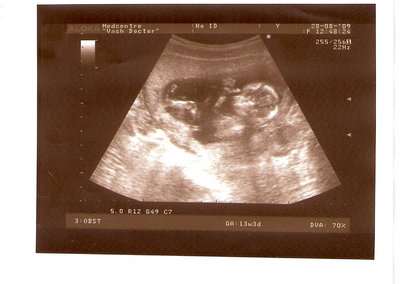

СЫН

| Вложения: |

2.jpg [ 110.14 КБ | Просмотров: 2450 ]

Nikisa писал(а): Foto prosto chudesnoe. A na kakom sroke uznali, chto sin.............. НА 13 НЕДЕЛЯХ.КАК РАЗ ВОТ В ЭТО узи, ОНО УМЕНЯ ВТОРОЕ БЫЛО. ЭТО КОНЕЧНО МАЛЕНЬКИЙ СРОК ДЛЯ ОПРЕДЕЛЕНИЯ ПОЛА. НО Я ПОПРОСИЛА ВРАЧА(ЭТО КТСТАТИВ РОССИИ БЫЛО) ХОТЯ БЫ ПРЕДПОЛОЖИТЬ. ЕЙ ВСЁ ТАКИ УДАЛОСЬ РАССМОТРЕТЬ.НУ ВООБЩЕМ ЧЕРЕЗ НЕСКОЛЬ ДНЕЙ ПОЙДУ К ВРАЧУ, УЖЕ АМЕРЕКАНСКОМУ И УЗНАЮ ТОЧНО. К ТОМУ ВРЕМЕНИ У МЕНЯ БУДЕТ СРОК 18 НЕДЕЛЬ. ХОТЕЛОСЬ БЫ ПОСМОТРЕТЬ НА ДРУГИЕ ФОТО НА ЭТОМ СРОКЕ ИЛИ БОЛЬШЕ. ТАК ЧТО ВЫКЛАДЫВАЙТЕ, ЕСЛИ НЕ ЖАЛКО!